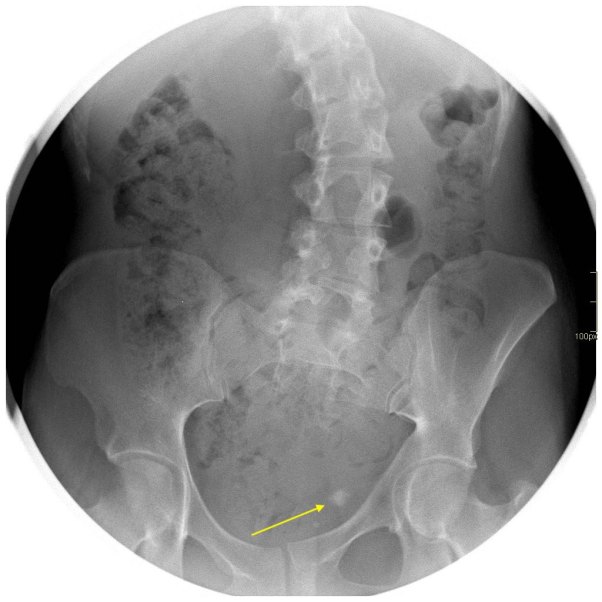

Cuando tu ves el estudio que te he enseñado, ¿Qué piensas?. Lo más normal es que pienses que el paciente, tiene una litiasis yuxtavesical izquierda, que observas en la placa simple de la imagen 2, corresponde con la imagen del TAC de Abdomen sin contraste, en la imagen 1. En el contexto de su patología, al paciente se le realiza una cistografía para valorar reflujo, que se demuestra en la imagen 3 y la imagen 4, donde puedes ver la existencia de reflujo en lado derecho, que tiñe el riñón derecho.

Finalmente, para hacerlo todo más verosímil, observas la ecografía donde ves cortes transversos y longitudinales donde ves una imagen hiperecogénica con una sombra posterior marcada, justo anclada la unión ureterovesical izquierda, al colocar el color en esa localización, podemos ver la típica imagen de artefacto de centelleo, que marca claramente la presencia de una litiasis en otros tanto estudios, imágenes 5 y 6.

Las flechas amarillas indican las regiones donde puedes encontrar la semiología que es la base del post de hoy.